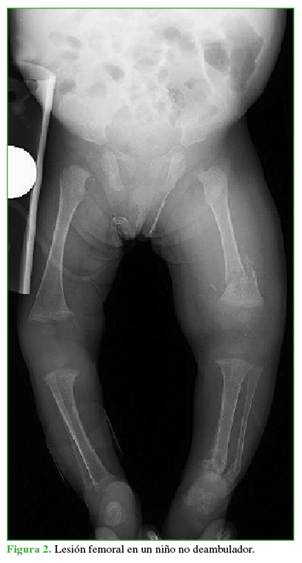

4.       Las fracturas femorales por abuso son más probables en niños que aún no caminan (Figura 2).

5.       Las fracturas de la diáfisis media son las fracturas femorales más comunes en situaciones de abuso y no abuso.